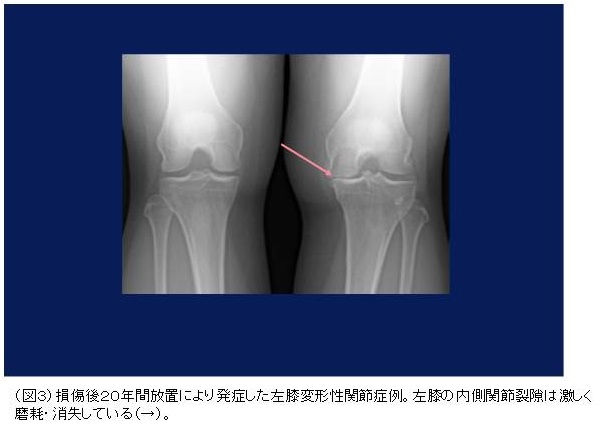

しかしながら、このような不安定膝となっても、日常生活、歩行や軽い疾走が可能であることが多く、時に膝くずれを繰り返します。このように放置された場合、半月板損傷を合併し、引っ掛かりやロッキングを来すようになります。さらに放置すると関節軟骨の磨耗、変性を来し、若くして変形性関節症となり日常生活に支障をきたすようになります。